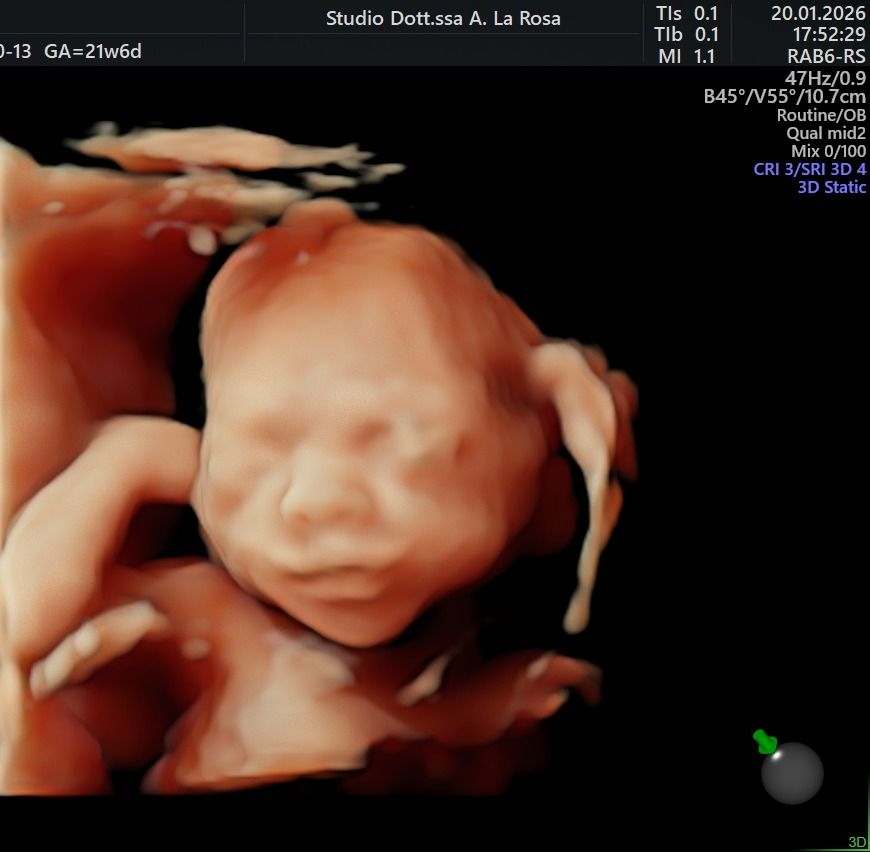

Nel corso della mia lunga esperienza lavorativa in ospedale,  ho maturato una particolare competenza nella gestione delle gravidanze a rischio sia per problematiche materne che fetali, nella diagnostica prenatale sia invasiva ( amniocentesi, villocentesi) con all'attivo migliaia di procedure effettuate, che nella diagnostica strumentale ecografica ( ecografie ostetriche di I e II livello, test combinato, studio della Translucenza nucale, DNA fetale, studio doppler flussimetrico dei distretti materni e fetali ).

Foto e video